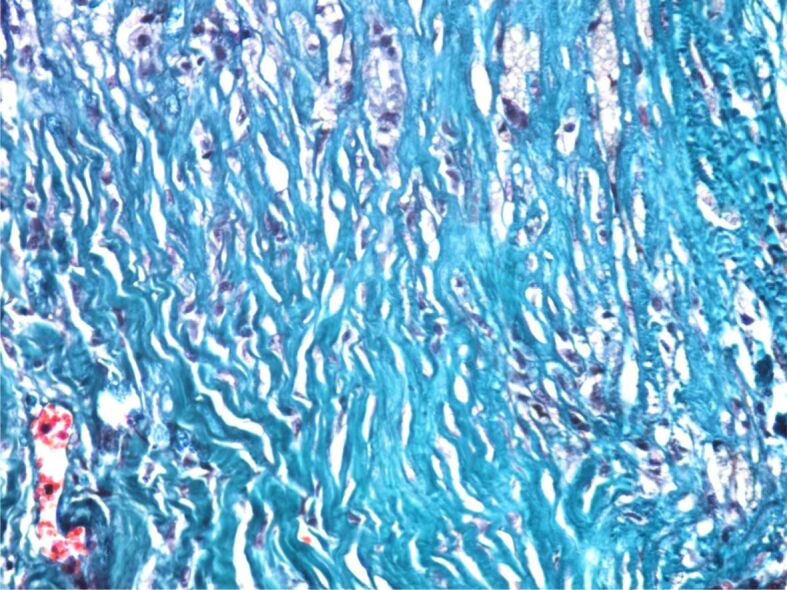

动脉瘤的定义是动脉壁扩张,直径超过相关血管正常直径的 1.5 倍。主动脉瘤(AA)可发生在任何部位,但大多位于腹部和肾下部,并延伸至髂动脉。主动脉瘤通常没有症状,最常见的情况是在对其他疾病进行各种成像检查时偶然发现。AA 的破裂通常很剧烈,是导致心脏性猝死的原因之一。手术治疗以及最近的血管内治疗是修复 AA 的唯一有效方法。在这项研究中,我们对有冠状动脉造影指征的稳定型劳累性心绞痛患者进行了 AA 诊断筛查。研究于 2021-2023 年期间在罗马尼亚蒂米什瓦拉心血管疾病研究所进行。在需要进行冠状动脉造影的 2458 名劳累性心绞痛患者中,有 1844 名患者(75%)至少有一个动脉粥样斑块狭窄,其中 312 名患者有 AA,其中 173 名患者位于腹主动脉水平。

An aneurysm is defined as a dilation of the arterial wall with a diameter exceeding 1.5 times the normal diameter of the vessel concerned. Aortic aneurysms (AAs) can develop at any level but are mostly found at the abdominal and infrarenal levels and extend to the iliac arteries. AAs are usually asymptomatic and are most often discovered incidentally during various imaging investigations for other conditions. Rupture of an AA is usually dramatic, being one of the causes of sudden cardiac death. Surgical treatment and, more recently, endovascular treatment are the only effective methods of AA repair. In this study, we screened for the diagnosis of AAs in patients with stable exertional angina who had indications for coronary angiography. The study was carried out in the period 2021-2023 in the Institute of Cardiovascular Diseases Timişoara, Romania. Of the 2458 patients with exertional angina who required coronary angiography, a number of 1844 (75%) patients had at least one stenotic atheromatous plaque, and of these 312 patients had AAs, of which 173 at the level of the abdominal aorta.